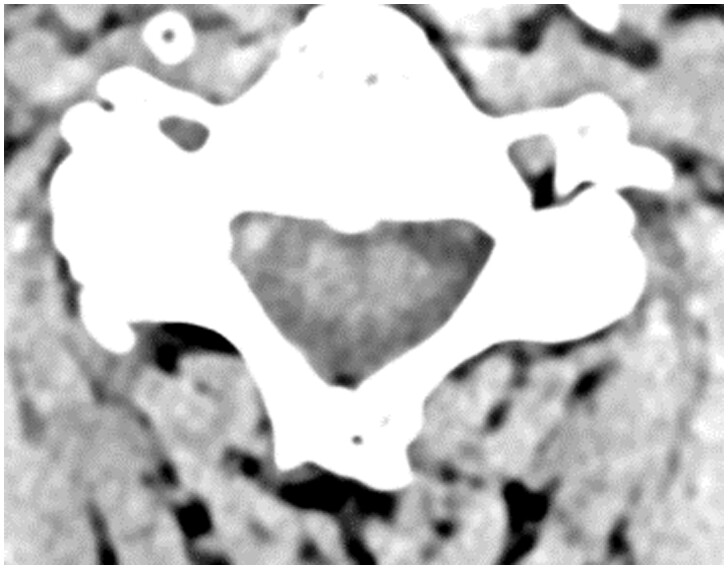

Hyperpneumatization is a rare pathological process where air-filled cavitation form within solid bone architecture occurring at sites where physiological pneumatization is not seen. Extension of this process into the atlanto-occipital region is considered extremely rare and is only quoted several times in the literature. In this case report, we present a 66-year-old man who presented with an 8-month history of a worsening frontal headache and blocked sensation in his left ear. Subsequent CT head evaluation revealed hyperpneumatization affecting C1 vertebra, temporal and occipital bones with extension into the clivus. A rare complication of epidural emphysema was seen. The aetiology of hyperpneumatization is uncertain, although it is thought to be either congenital or acquired. In our case, clinical suggestion of eustachian tube dysfunction and radiological findings of thickened sinus mucosa and a unilateral nasal polyp point to chronic recurrent coryzal illnesses, which may indicate an acquired mechanism. Management is mostly conservative with surgical management reserved for high risk or refractory cases.